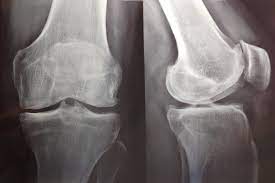

Este ensayo clínico aleatorizado reveló que, en pacientes con artrosis de rodilla sintomática y derrame-sinovitis, la diacereína (50 mg dos veces al día) durante 24 semanas no produjo una mejoría mayor del dolor de rodilla en comparación con placebo. Estos hallazgos no respaldan el uso de diacereína para el tratamiento del dolor de rodilla en esta población. JAMA Intern Med, 2 de marzo de 2026